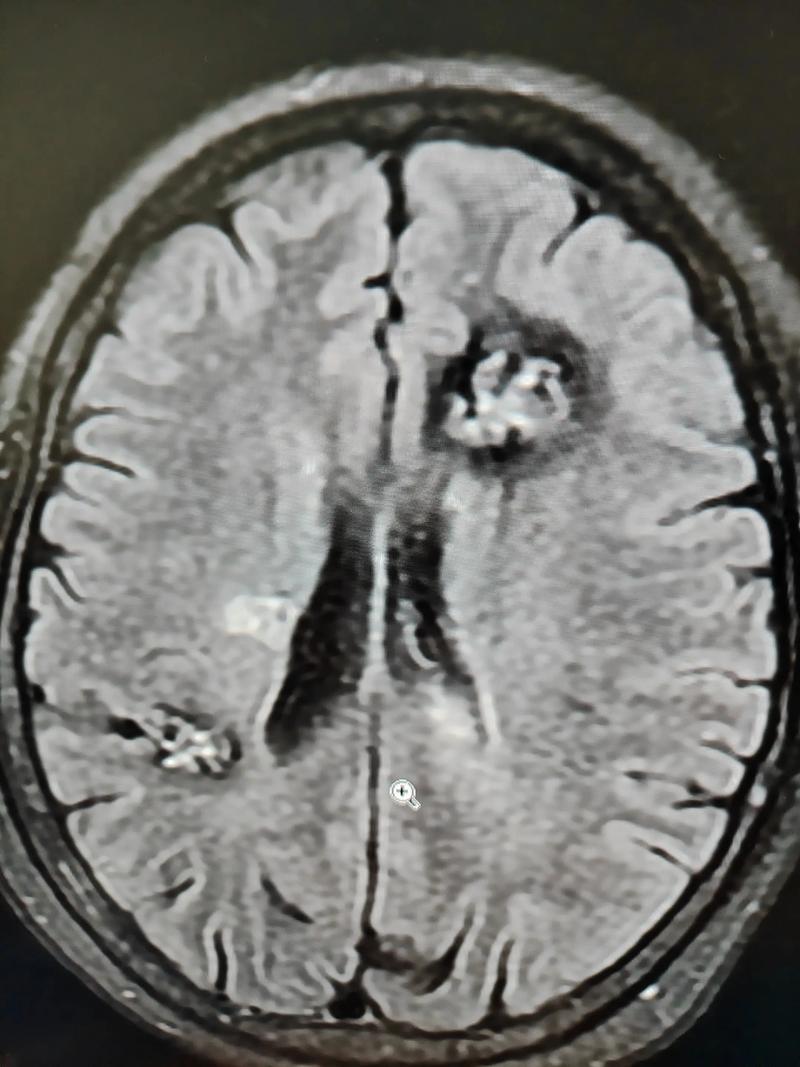

这是最常见的原因,脑梗和脑肿瘤在CT或MRI(磁共振)影像上有时会表现相似,都表现为“脑内占位性病变”或“异常信号”。

- 急性期脑梗:在发病后的最初几天,由于脑组织急性水肿,影像上可能看起来像一个肿瘤,周围有明显的占位效应,医生称之为“假性肿瘤”。

- 脑梗后的出血性转化:有些脑梗患者,特别是大面积脑梗,在治疗过程中梗死区域可能会因为血流再通等原因发生出血,形成“出血性脑梗”,这在影像上也会表现为混杂信号的占位性病变,容易与肿瘤内出血混淆。

当影像学检查发现一个“可疑病灶”时,医生需要结合病史、发病速度、影像特征变化,甚至进行活检来最终判断,究竟是脑梗的演变、出血转化,还是一个真正的脑肿瘤。